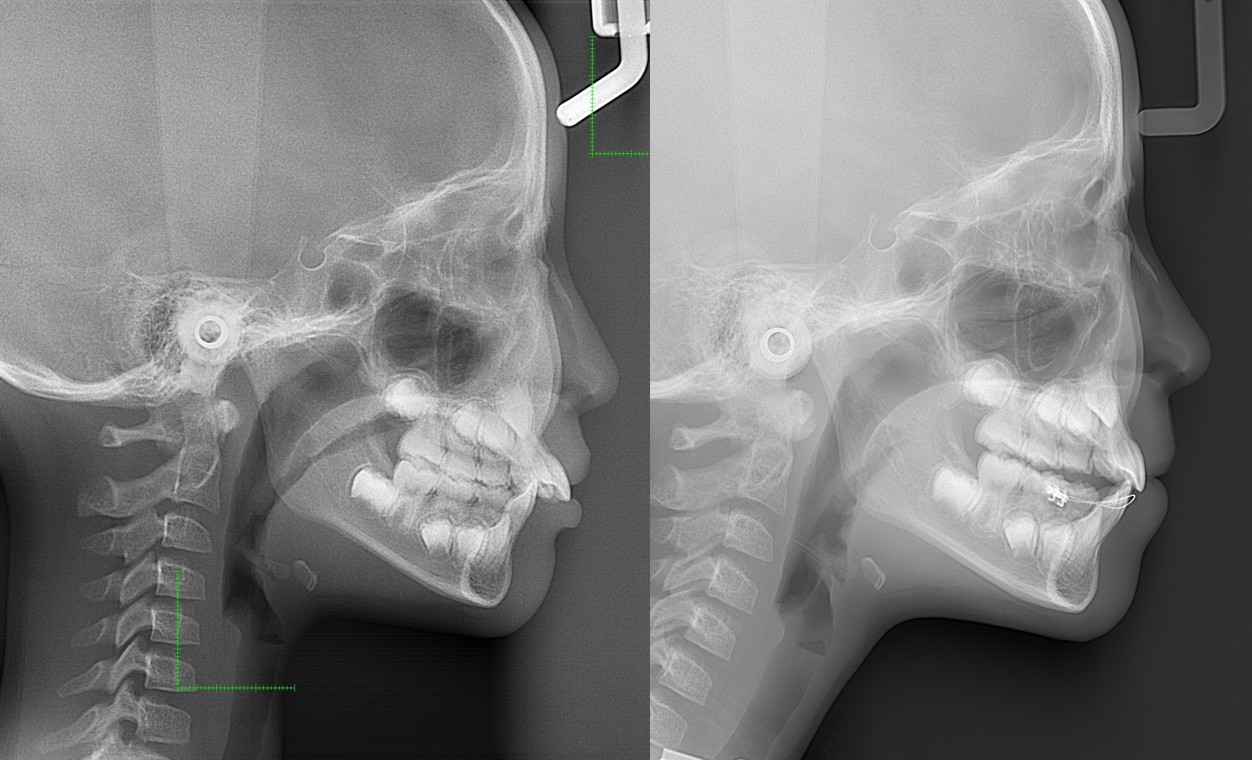

顎変形症:下の歯(顎)が出ている。また、下顎側方偏位:(あごまがり)である

下顎側方偏位:あごまがり

噛んだときに上下の歯が左右にずれているまたは顎が左右にずれている場合、 咬む癖や、小児期の癖、現在かぶせものをしているものの問題等があります。 場合によっては顎の痛みが伴うこともあります。

・下顎側方偏位

・上顎の突出・後退

・下顎骨突出・後退

・顎変形症に伴う顔貌の積極的な改善

・主訴:下あごが出ている。顎が曲がっている。

・診断:骨格性下顎前突

・年齢:20歳

・使用した主な装置:マルチブラケット装置

・抜歯部位:第一小臼歯を4本抜去

・治療期間:30か月

・通院回数:30回

・費用の目安:保険適応。保険矯正代金は、20万円くらい。症状・期間によってかわります。その他大学病院で外科矯正手術代金がかかります。